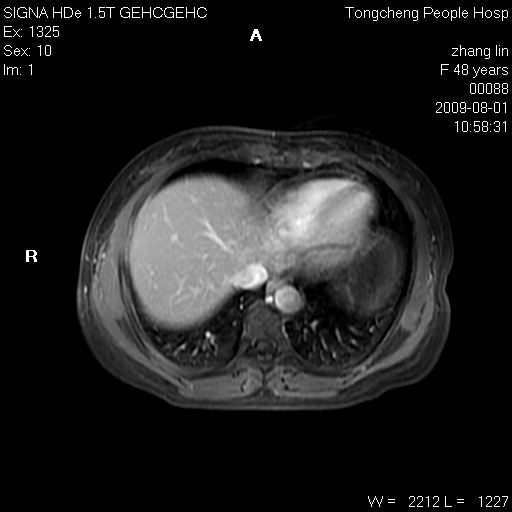

女,48岁。健康体检,彩超发现右肾占位性病变。平素健康。

临床诊断:右肾占位性病变,性质待定(囊肿?肿瘤?)。

上中腹部mr平扫+增强扫描,图像如下:

右肾上极见一类圆形病灶,t1wi呈等信号t2wi呈等高混杂信号,三期增强无强化,边界清---考虑囊肿出血。

同反相位均表现为等信号,病变无强化,考虑含蛋白的囊肿可能,弥散加权相或许有些帮助,